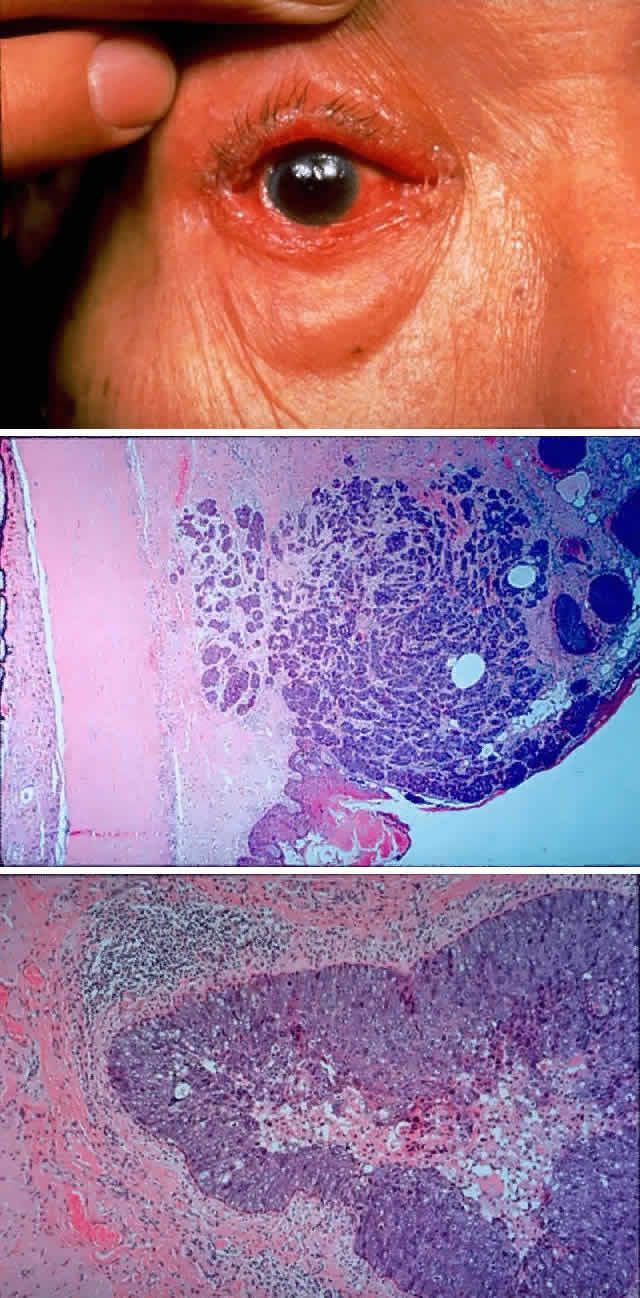

Fig. 11. A 61-year-old white man noted a pigment spot in the medial canthal area of his left eye associated with intermittent subconjunctival hemorrhages lasting 6 months. On examination, there was a raised, pigmented lesion in the lower medial conjunctiva (A) measuring 20 mm across the base, with a central, pale, telangiectatic nodule 6 mm thick noted on lateral gaze (B). There was extension into the upper medial fornix and laterally in the lower fornix. There was no evidence of preauricular, submandibular, or cervical lymphadenopathy. A clinical diagnosis of conjunctival melanoma arising in primary acquired melanosis (PAM) was made. Conjunctival biopsy revealed invasive melanoma (C and D) (H & E, × 80 and × 200, respectively) arising within PAM type IB (E) (H & E, × 200). A total exenteration and split-thickness skin graft from the anterior thigh were performed, and the patient was disease-free at 6 months' follow-up.

Fig. 13. A 65-year-old man presented originally with a right retinal detachment and secondary glaucoma due to a large choroidal melanoma. The patient refused enucleation and self-treated instead with herbal medicines and “health foods.” He presented again 6 years later with acute onset of proptosis associated with pain, periocular edema, erythema, and marked restricted ductions (A). CT scan revealed the intraocular tumor, with massive orbital extension and displacement of the globe anteriorly, downward, and laterally (B and C). He underwent lid-splitting exenteration and split-thickness skin graft from the anterior thigh. The gross specimen shows the massive orbital component of melanoma, which had extended from the posterior choroid through emissarial vessels (D). An area of predominantly spindle-shaped melanoma cells with scattered, heavily pigmented macrophages is shown (E) (H & E, × 200). (D and E courtesy of Valerie A. White, MD, Department of Pathology, University of British Columbia, and the Vancouver Hospital and Health Sciences Center.)